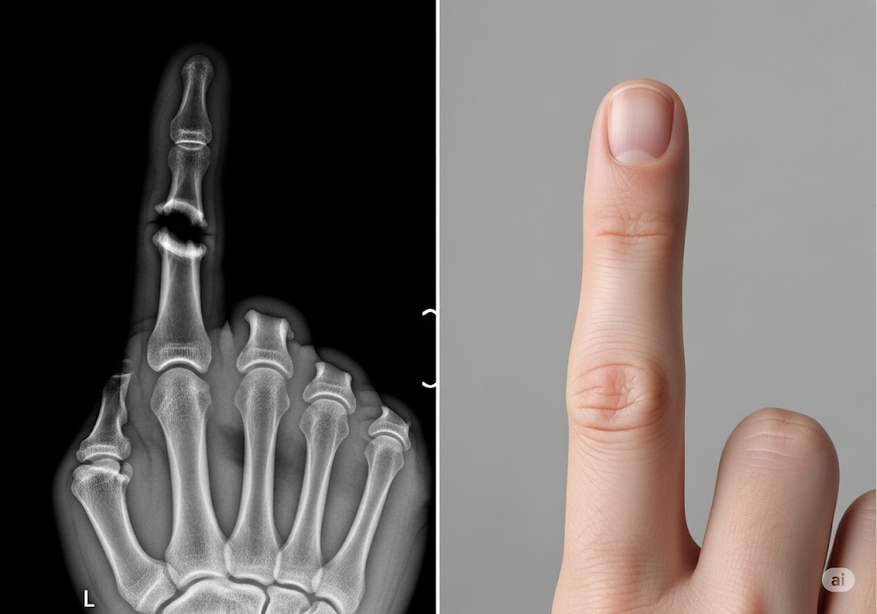

Научный подход компании базируется на применении протеина NELL-1, участвующего в физиологических процессах костеобразования. Лабораторные эксперименты зафиксировали уникальное свойство NELL-1 инициировать остеогенез исключительно в требуемых зонах, параллельно блокируя процессы адипогенеза.